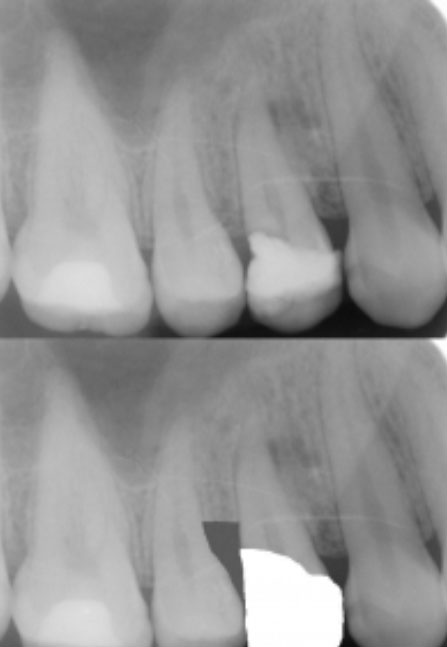

Dental crowns – Crown lengthening serves to provide more space between the supporting jawbone and dental crown. This prevents the new crown from damaging gum tissues and bone once it is in place.

Crown lengthening is normally performed under local anesthetic. The amount of time this procedure takes will largely depend in how many teeth are involved and whether a small amount of bone needs to be removed, in addition to the soft tissue. Any existing dental crowns will be removed prior to the procedure, and replaced immediately afterwards.

When the dentist is satisfied the teeth have sufficient exposure, the wound will be cleaned with sterile water and the gum tissue will be sutured with small stitches. The teeth will look noticeably longer immediately after surgery because the gums have now been repositioned.